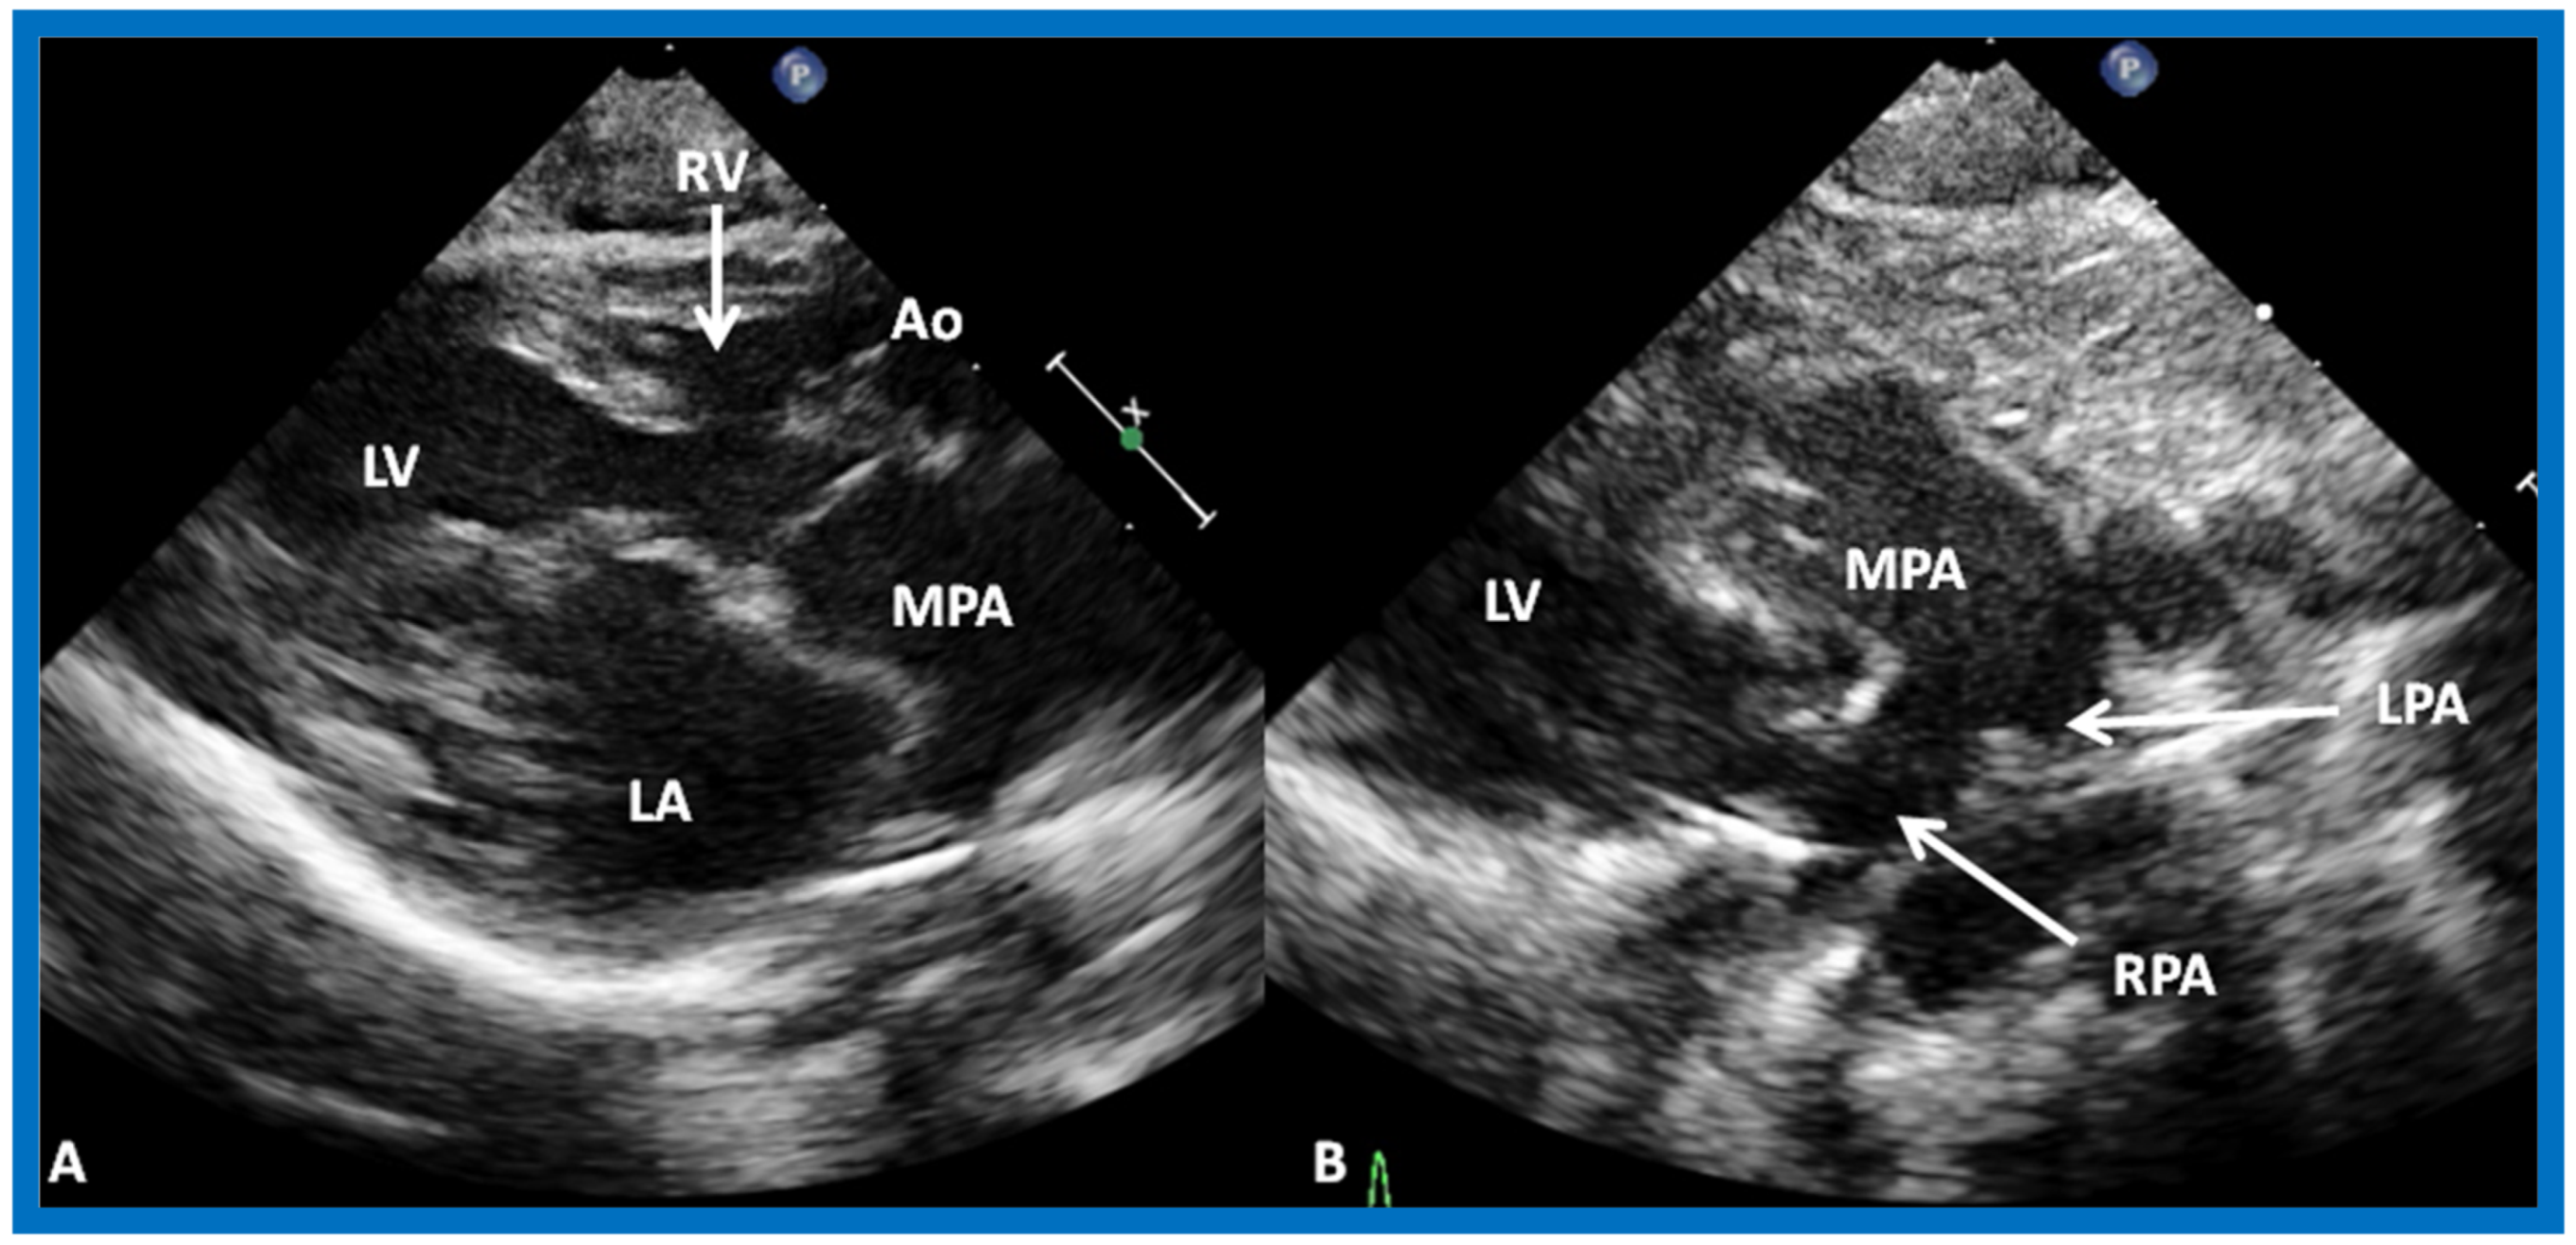

The relationship of the great arteries is examined next in order to classify them into various types [41]. The relationship of the great arteries is established by following the vessels arising from the ventricles until pulmonary bifurcation or aortic arch. In Type I patients with normally related great arteries, the aorta arises from the LV (Figure 20), while in Type II patients with transposition of the great arteries, the PA arises from the LV (Figure 21 and Figure 22). In Type III patients, it may be little more difficult to assign the great artery relationship, and sometimes angiography is needed. In type IV with truncus arteriosus, the limited data [22] suggest that this can be done by echocardiography (Figure 23 and Figure 24).

Figure 21.

(A) Selected video frame from precordial long axis views of a neonate with tricuspid atresia and transposition of the great arteries demonstrating the left atrium (LA), left ventricle (LV), a very small right ventricle (RV) and a moderate sized ventricular septal defect (not marked). The vessel coming off of the LV is traced in (B) and shown to bifurcate into left (LPA) and right (RPA) pulmonary arteries, confirming that this is the main pulmonary artery (MPA). Ao, Aorta. Reproduced from Rao P.S. [39].